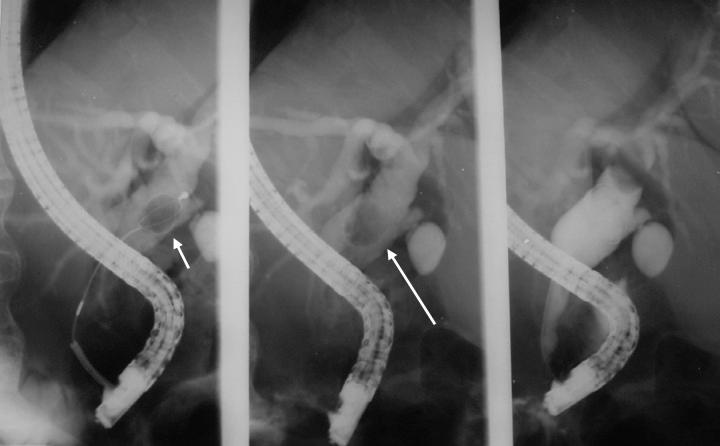

The indications were: CJ only in79, CJ and dilated ducts in 103, and CJ and biliary stones in 42. The ERCP findings were: (A) For those with CJ only: ERCP was normal in 45, showed dilated ducts with no stones in 13, dilated ducts with stones in 16, normal CBD with a stone in 1; (B) For those with CJ, dilated ducts: ERCP was normal in 17, showed dilated ducts with stones in 47, dilated ducts without stones in 28, normal CBD with a stone in 1, a choledochoduodenal fistula in 2; (C) For those with CJ and duct stones: ERCP was normal in 2, showed dilated ducts with stones in 21, dilated ducts without stones in 14, normal CBD with a stone in 1.

指征如下:单纯CJ 79例,CJ伴胆管扩张103例,CJ伴胆结石42例。ERCP检查结果如下:(A)对于单纯CJ患者:ERCP正常45例,显示胆管扩张但无结石13例,胆管扩张且有结石16例,胆总管正常但有结石1例;(B)对于CJ伴胆管扩张患者:ERCP正常17例,显示胆管扩张且有结石47例,胆管扩张但无结石28例,胆总管正常但有结石1例,胆总管十二指肠瘘2例;(C)对于CJ伴胆管结石患者:ERCP正常2例,显示胆管扩张且有结石21例,胆管扩张但无结石14例,胆总管正常但有结石1例。